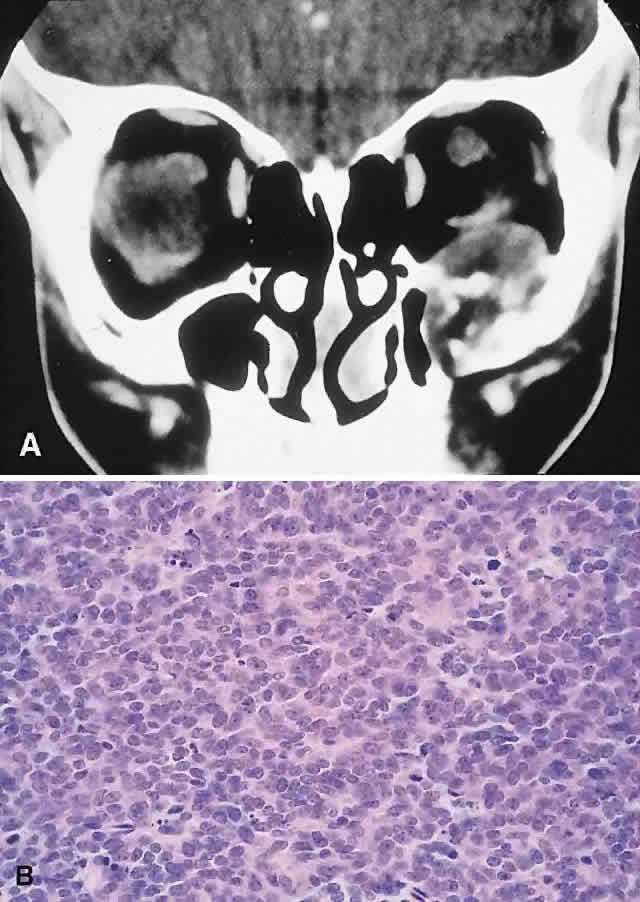

IMAGING. The CT appearance is of an expansile or permeating mass that shows mottled bone destruction (Fig. 11). There may be an associated soft tissue component.

Fig. 11. This 12-year-old boy experienced subacute left proptosis, vertical globe displacement, and lower lid edema. A. CT showed an expansile mass with mottled bone destruction of the orbital floor. B. Biopsy revealed a Ewing's sarcoma consisting of densely packed and mitotically active small round cells (hematoxylin-eosin, × 80).